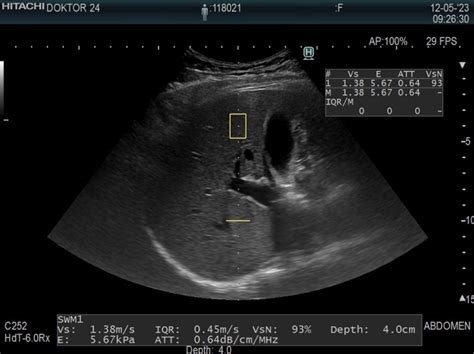

Ko se par sooči s težavami pri zanositvi, je prvi korak obisk izbranega ginekologa. Ta opravi osnovna testiranja, ki lahko pomagajo pri ugotavljanju vzroka neplodnosti. Če so izvidi normalni in je par še relativno mlad, ginekolog pogosto predlaga terapijo s kontroliranimi spolnimi odnosi. Kot pojasnjuje dr. Aleksander Merlo, dr. med., spec. gin. in por., direktor Bolnišnice Postojna, se pri tej metodi z ultrazvokom spremlja rast foliklov pri ženski, sledijo pa kontrolirani spolni odnosi v času ovulacije. Če naravne poti niso uspešne, lahko ginekolog predpiše t. i. "stop injekcijo" (hCG), ki spodbudi sproščanje jajčeca, in ponovno svetuje kontrolirane odnose.

Ena izmed teh metod je intrauterina inseminacija (IUI). Ta postopek se uporablja pri parih, kjer je ženska mlajša, težave pa vključujejo nepojasnjeno neplodnost, blago obliko moške neplodnosti, motnje ovulacije ali neprimerno sluz v materničnem vratu. Postopek vključuje spremljanje rasti foliklov z ultrazvokom, spodbujanje ovulacije z injekcijo hCG, pripravo partnerjevega semena v laboratoriju in nato prenos koncentriranih, gibljivih semenčic v maternično votlino med ovulacijo. Uspešnost enega postopka IUI znaša približno 10 %, pri čemer se priporoča opraviti tri postopke, preden se preide na zahtevnejše metode.

Če inseminacija ni uspešna ali ni primerna, se uporabi klasični postopek IVF (In Vitro Fertilization). Ta se začne z vsakodnevnimi injekcijami hormonov, ki spodbujajo jajčnike k razvoju več foliklov in s tem več jajčnih celic. Po injekciji, ki sproži ovulacijo, sledi punkcija jajčnih celic, partner pa odda seme. V laboratoriju embriolog pripravi seme in ga doda jajčnim celicam, kjer pride do naravne oploditve. Zarodke nato oskrbujejo v inkubatorju tri do pet dni, preden se izvede prenos enega ali dveh zarodkov v maternico. Preostali zarodki se zamrznejo za morebitne prihodnje postopke. Uspešnost metode IVF po enem ciklusu se giblje med 25 in 30 %.